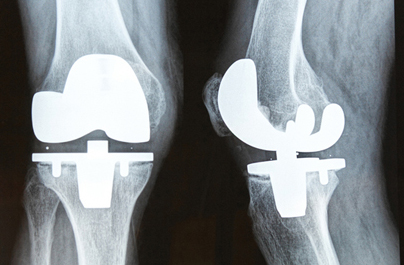

Her company gave her a viable option that saves everyone money. She is on her way to Costa Rica where she has a ten day, all expenses included, stay in a 4 star resort to prepare and recover from her operation. Joining her is a fellow coworker, Gary. He is going for a knee replacement at the same private hospital. While he was prepared to have to deal with knee pain because of the cost of the procedure, he is glad to have this option. It means he will be able to do more of what he wants to do during his retirement and without slowing his wife down.

A reporter followed them and saw that much of the equipment used was made in the U.S. A partial knee replacement device costs $45,000 in the States and only $3,000 in Costa Rica, though it’s from the same company.